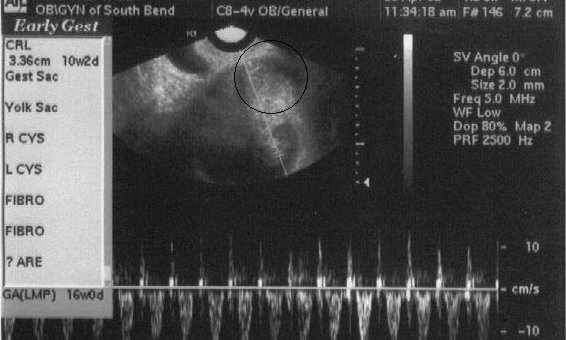

| This picture is even more difficult to see since they added the heartbeat at the bottom, but that is sort of cool in and of itself. The black circle on the picture this time is meaningless, but I can't figure out how to remove it! However, if you look straight down from the center of the circle, you will again see two white lines, which again show where the heartbeat is. The baby has grown in size 3 times since the last picture was taken! Click here to read about the day we had this ultrasound taken. (April 30, 2002 - 10 weeks, 2 days) |